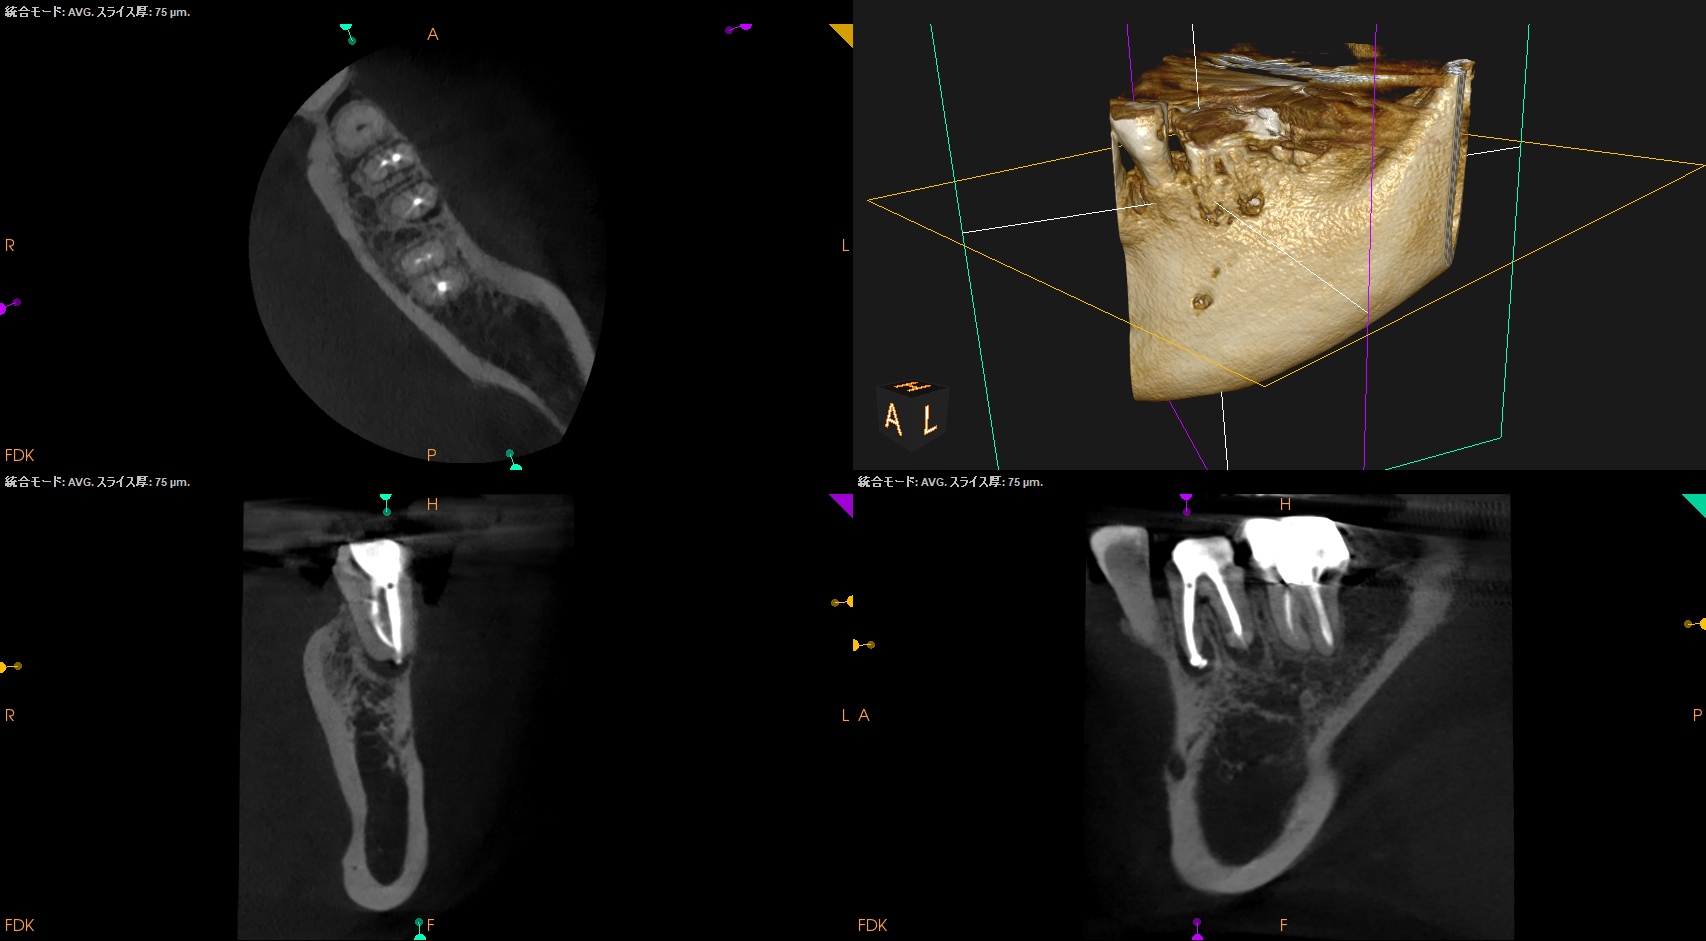

CBCT(2025.9.16)

MB

ML

D

MにもDにも病変がある。

B

頬側の骨がない。

これが圧痛に対する反応の原因だ。